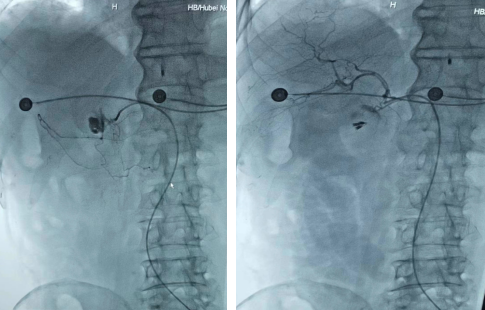

抵达阳逻后发现,病人的情况比想象中更糟糕,刚上手术台就发生了心跳骤停,测不出血压。介入团队立即投入抢救,与阳逻重症病房及麻醉科医生紧密配合,为患者实施了气管插管、球囊辅助呼吸及心肺复苏等抢救措施。患者呼吸、心跳恢复后,血压仍靠升压泵及大量输血维持。这种情况下手术风险极大,无论手术与否患者都有可能随时死亡,但如果能快速止血,或许病人还有活下去的希望。放射科介入团队在取得家属同意后,甘愿冒大风险为患者紧急实施消化道介入栓塞手术。术中,刘良进与吴良龙通力合作,在极短的时间内精准找到出血点,一边栓塞一边关注患者生命体征变化。奇迹发生了,患者血压可以测出87/31mmHg,心率在78次/分,十几分钟后,血压逐渐回升,维持在112/62mmhg,患者恢复了意识。目前,患者已经转入ICU病房继续观察治疗,急性出血已经停止,生命体征平稳。